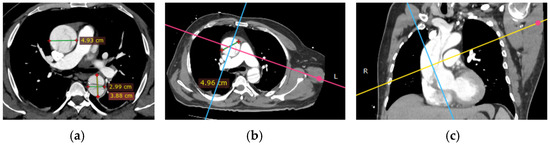

All patients received TTE upon admission. The assessment was conducted on left ventricular ejection fraction (LVEF), the presence of pericardial effusion, and wall motion abnormalities. The dimensions of the aorta and the presence of aortic valve pathology were recorded. CTA was conducted on all patients to verify the diagnosis of dissection, determine the extent of dissection (including the ascending aorta, aortic arch, and descending aorta), and assess for complications such as periaortic hematoma, rupture, or involvement of visceral arteries. Scans utilized a 128-slice CT scanner with contrast enhancement to delineate both true and false lumens. One of the critical aspects of evaluating aortic pathologies is the accurate visualization of the aortic lumen and wall structures through CT imaging. However, non-gated CT scans are susceptible to pulsation artifacts, which can obscure essential details and lead to diagnostic challenges. Common pulsation artifacts observed in this study are illustrated in Figure 2.

Figure 2. Artifacts in non-gated computed tomography: pulsation effects in aortic imaging: common artifacts from pulsation in non-gated computed tomography (CT) imaging are highlighted with green arrows (b,c). These artifacts can obscure critical details of the aortic wall and luminal structure, potentially complicating the assessment of aortic dissections (a,d). Accurate interpretation requires recognizing and mitigating such limitations.